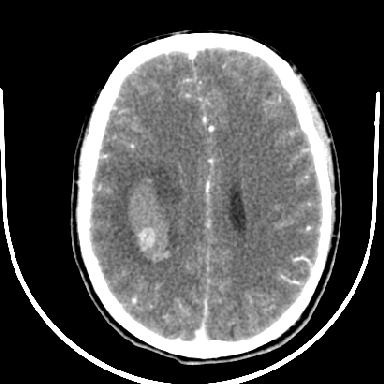

考虑高血压性脑出血,依据:

1是高血压性脑出血的好发部位,形态呈肾形,是高血压性脑出血的常见形状

2增强时占位效应加重了,考虑出血还没有停止

3病灶周围水肿不是太厉害,一般肿瘤出血水肿多非常明显

4病灶周围的‘软组织’影没有明显的强化

5至于脑血管畸形引起的出血,暂时没有看到明显的畸形血管影,也不太支持

支持右侧基底节脑出血

右侧基底节区脑出血.

支持右侧基底节区(主要为外囊区)原发性脑出血。

另附部分资料:“血液溢出血管外形成血肿,其内含有大量血红蛋白、血浆白蛋白,球蛋白,因这些蛋白对x线的吸收系数高于脑质,故ct呈现高密度阴影,ct值达40~90h,最初高密度灶呈非均匀一致性,中心密度更高,新鲜出血灶边缘不清。基底节区血肿多为“肾”型,内侧凹陷,外侧膨隆,因外侧裂阻力较小,故向外凸,其它部位血肿多呈尖圆形或不规则形”